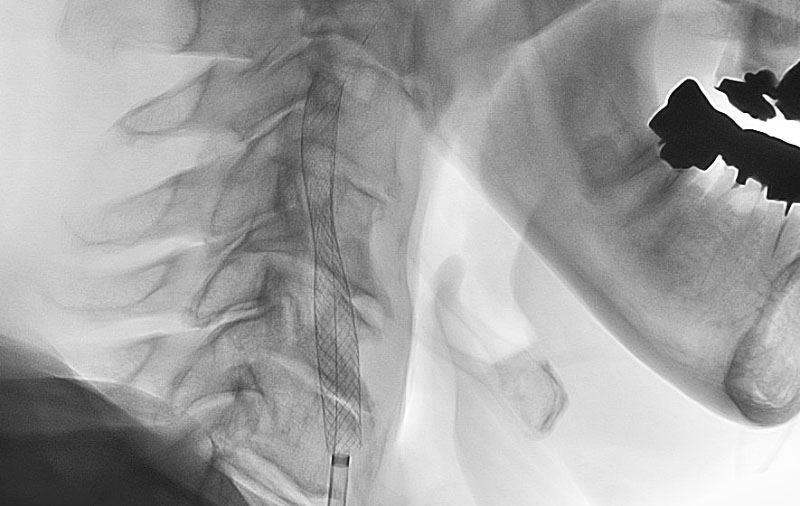

No.1594 手術前